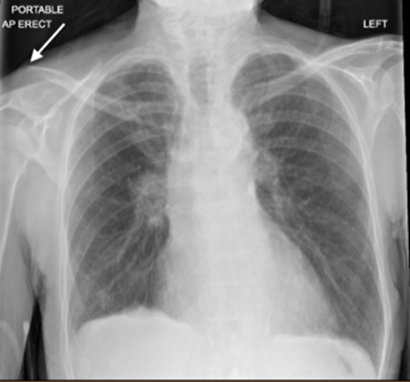

A 73-year-old female presents to the emergency department (ED) with right-sided clavicular pain. She was recently diagnosed with a right clavicle fracture (Figure 1) and was discharged home with a sling and oral analgesia. The patient returned to the ED due to persistent severe pain despite taking her oral medication. On physical examination, the patient appeared uncomfortable, and a deformity was noted with tenderness to palpation along the distal aspect of the right clavicle. The patient had a very limited active range of motion of the right upper extremity, with a maximum shoulder abduction of 10-15 degrees, limited due to pain. The ED physician performed a superficial cervical plexus nerve block (SCPNB) with ultrasound guidance, and the patient had a complete resolution of pain within 15 minutes. Range of motion also improved, with near 180-degree shoulder abduction achieved.

Figure 1. Patient’s X-ray demonstrating right clavicle fracture